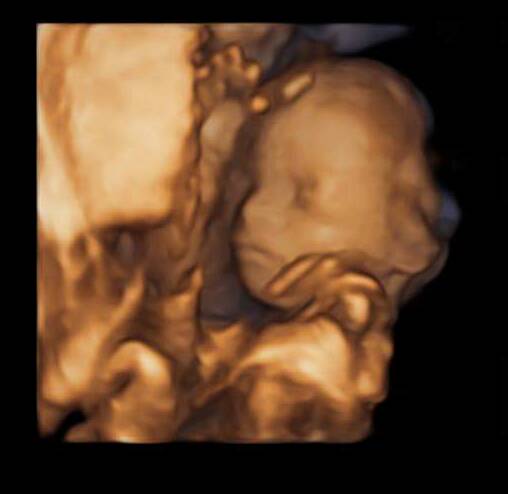

Madzia chłopak jak się patrzy, jednak faktycznie u mnie nie było widać takiego przyrządu